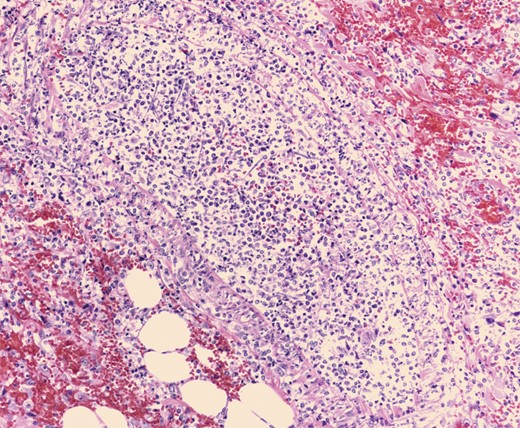

Pathologic evaluation of the resected bowel revealed hemorrhagic, gangrenous bowel (Fig. 1) and granular friable, ulcerated mucosa (Fig. 2). Microscopically, there were areas of transmural bowel necrosis (Fig. 3) and fungi within the bowel wall, artery wall and lumen (Fig. 4). Gomori Methenamine Silver stain was characteristic of Aspergillus species (Fig. 5).

Mononuclear cells associated with scattered neutrophils and prominent fungal hyphae in subserosal arteries and invading vessel walls.